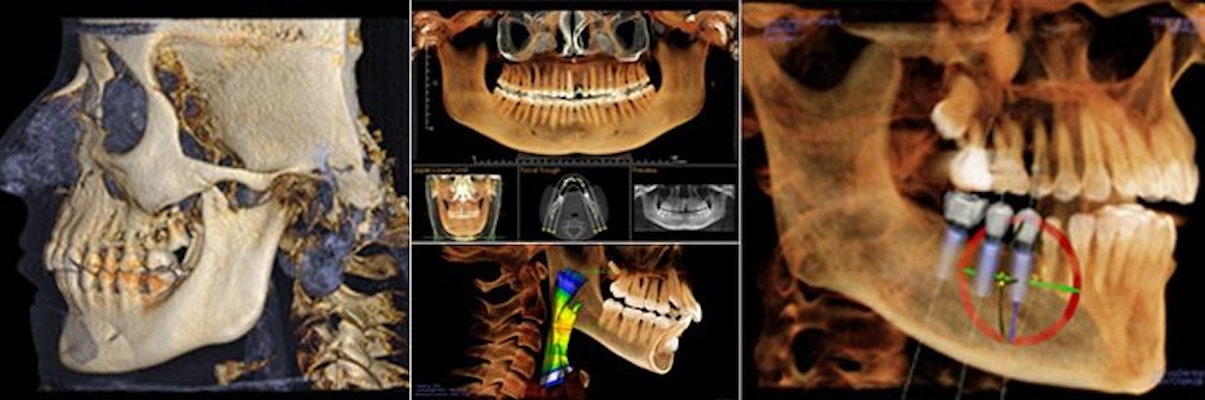

3D Imaging with Sirona XG3D

Cone Beam Volumetric Topography (CBVT, sometimes referred to as CBCT) allows us to quickly and safely diagnose many conditions related to your oral health. It also allows us to accurately image vital anatomical structures, making implant placement and surgical procedures safer.

All of this is accomplished with an extremely low effective dose to you. Depending on the field of view and resolution required, the dose is similar to two round trip flights from New York to Los Angeles, or roughly 0.28 mSv. Click on the video below for more information about the Sirona XG3D

ORTHOPHOS XG 3D. The most popular x-ray unit in the world. Now with 3D. With a perfectly designed 3D cylinder volume of 8 cm in diameter and 8 cm in height and a standard resolution of 160 µm, ORTHOPHOS XG 3D is precisely tailored to the everyday routines of private practices: it can capture the patient's whole jaw in a single span.